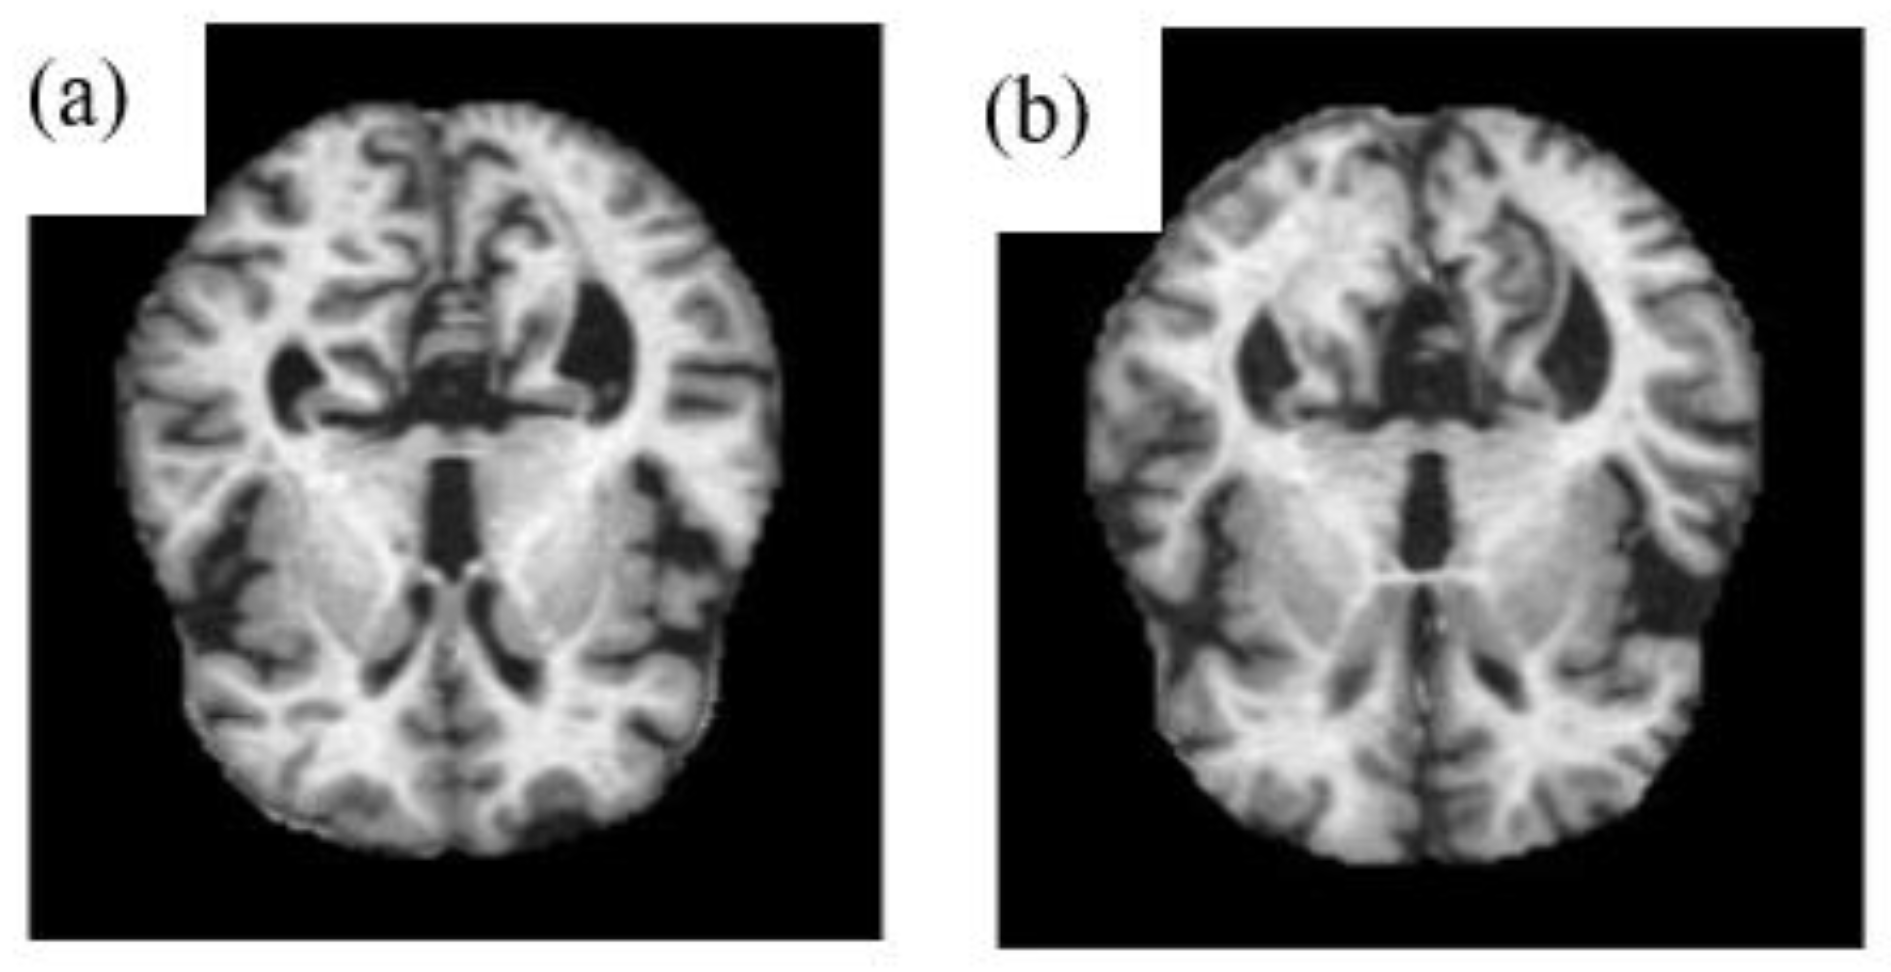

2.1. Pre-Processing

3.1. Dataset

3.2. Training and Testing